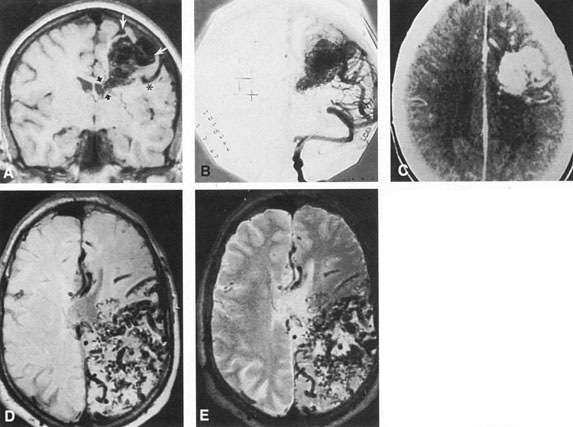

The detection of intracranial AVMs is facilitated by CT scanning and MRI (Fig. 10),88 but optimal management requires selective angiography89 that assesses the size and configuration of the mass, the number and location of feeding arteries, the flow characteristics and degree of steal from brain parenchyma, and the pattern of venous drainage.

Fig. 10. Neuroimaging of arteriovenous malformation. A: Coronal magnetic resonance imaging (MRI) (TR, 600 ms; TE, 20 ms) shows wedge-shaped vascular mass extending from the surface of the parietal cortex (white arrows) to the lateral ventricle (black arrows; asterisk, arterial feeder). B: Posteroanterior left arteriogram of the same lesion. C: Axial computed tomography scan with contrast enhancement. D: Axial MRI of a large arteriovenous malformation, first echo (TR, 2000 ms; TE, 20 ms). E: Second echo (TR, 2000 ms; TE, 90 ms). (From Smith HJ, Strother CM, Kikuchi Y, et al: MR imaging in the management of supratentorial intracranial AVMS. AJNR Am J Neuroradiol 9:225, 1988.)

The natural history of unruptured intracranial AVMs is somewhat controversial,65,67 the issue being conservative management of interventional therapy using refined microsurgical or embolization techniques. Brown and associates90 reviewed the experience of the Mayo Clinic, Rochester, Minnesota, from 1974 through 1985, with a minimal follow-up of at least 4 years after diagnosis (mean follow-up time, 8.2 years). Of 168 patients, 18.5% had an intracranial hemorrhage, with an overall risk of hemorrhage of 2.25% per year (vs. 4%, as reported by Ondra et al65), and observed annual rates of hemorrhage increased over time. The mortality rate from hemorrhage was 29%. Of 22 patients with nonfatal intracranial hemorrhages, 14 did not undergo treatment and none of these had recurrent hemorrhage during the mean follow-up of 58 months. No radiologic or clinical features seem consistently helpful in predicting rupture. According to Pollock et al,61 analysis of clinical and radiologic features revealed 6 signficant risk factors for hemorrhage: (i) history of prior bleeding; (ii) deep location; (iii) deep venous drainage; (iv) increasing patient age; (v) diffuse morphology (versus compact nidus); and (vi) single draining vein. Based on these findings, these authors concluded that annual bleeding for the low-risk group was 1.0%, and it was 9.0% for the highest risk group.